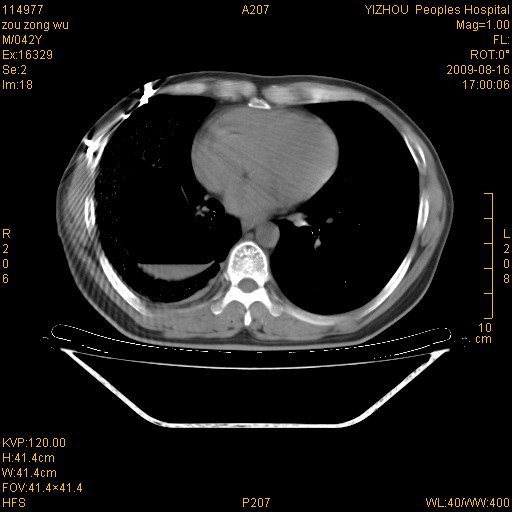

以下是引用zjzjr在2009-8-17 10:42:00的发言:[br]右侧间质性肺炎伴纤维化,右肺下叶肺囊肿伴感染(不除外外伤后引起),右肺野及胸壁软组织\\肝内见多发斑点状,中枪了吧.右侧胸膜肥厚\\粘连.